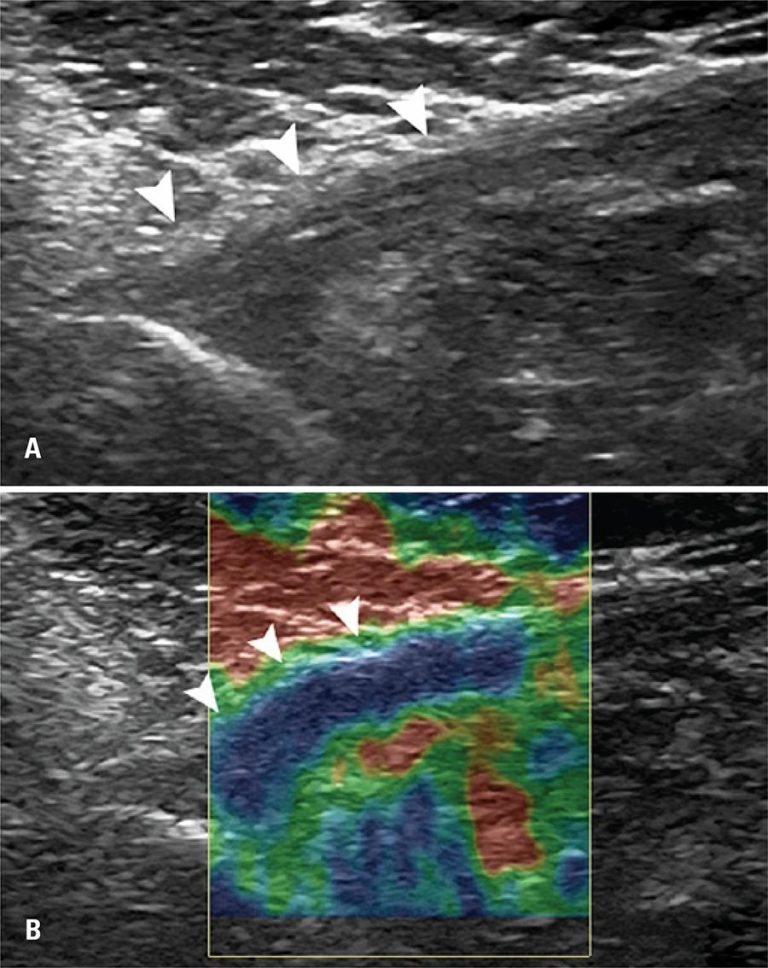

Participaram do estudo 20 sujeitos, sendo 10 com ruptura do tendão do músculo peitoral maior e 10 como controles. Avaliou-se o tendão músculo peitoral maior contralateral por meio de exames ultrassonográficos e elastografia. O aparelho de ultrassonografia utilizado era de alta resolução, e a avaliação foi realizada no modo B. A avaliação por elastografia foi classificada em três padrões, a saber: (A) se endurecido (mais de 50% de área com coloração azul); (B), se intermediário (mais de 50% verde); e (C), se amolecido (mais de 50% vermelho).